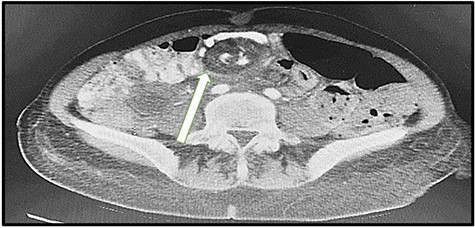

A 43-year-old lady was seen at the Surgical Accident and Emergency Department with a 14-day history of severe colicky abdominal pain, nausea and vomiting. She had a background history of LRYGB in 2011 and laparoscopic repair of internal hernia in 2017. Upon admission, her vitals were pulse (P): 86 bpm, blood pressure (BP): 120/80 mmHg and temperature (T): 37.5. The patient appeared to be malnutrition and dehydrated. Abdominal examination, mild distension, epigastric and para-umbilical tenderness and digital rectal exam (DRE) was empty. Intravenous fluids were administered and laboratory tests were sent. Full blood count (white blood count (WBC): 11.5 109 g/l, HB: 12.0 109 g/l and platelet: 373), kidney profile (creatinine: 37 and urea: 2.1) and lactic acid were high (2.28). We ordered a computed tomography (CT) scan that immediately showed dilated bowel loops with crowded engorged mesenteric vessels showing swirling sign at the paramedian plane, with fluid surrounding the intestinal loops, suggestive of high-grade small bowel obstruction due to internal hernia (Fig. 1). The radiologist compared this result with the CT findings of 2017, which showed the same mesenteric swirling of vessels with a lymph node (Fig. 2). The surgical team discussed the result with the patient, and we obtained consent for exploratory laparotomy.